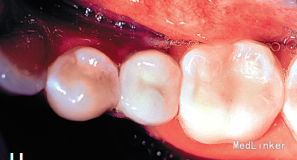

2年正畸治疗结束后,乳磨牙仍在。一年以后,患者18岁成年,拔除乳磨牙,植入植体,半年后套冠,效果很好,患者满意。有些先天缺失第二前磨牙的患者,若第二乳磨牙比较健康,可以减径后树脂修复参与正畸治疗,这样有保存骨量,维持牙弓间隙,保持与对合牙功能接触以免对合牙伸长的作用。骨量的保存利于植体的植入。